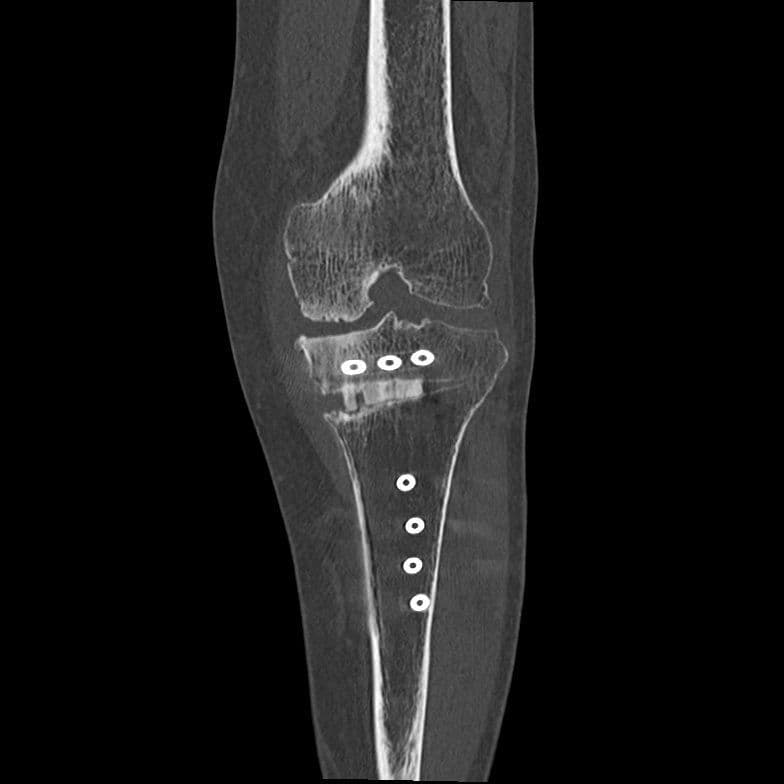

3D画像

撮影した画像から・・・

3D画像は撮影したCT画像を立体的に表示できるため、直感的に解剖学的情報や骨折部位などを把握することができ、診断や治療の助けになっています。出血や脳梗塞などによる緊急IVR検査を迅速に正確に行う為にもとても重要な画像です。